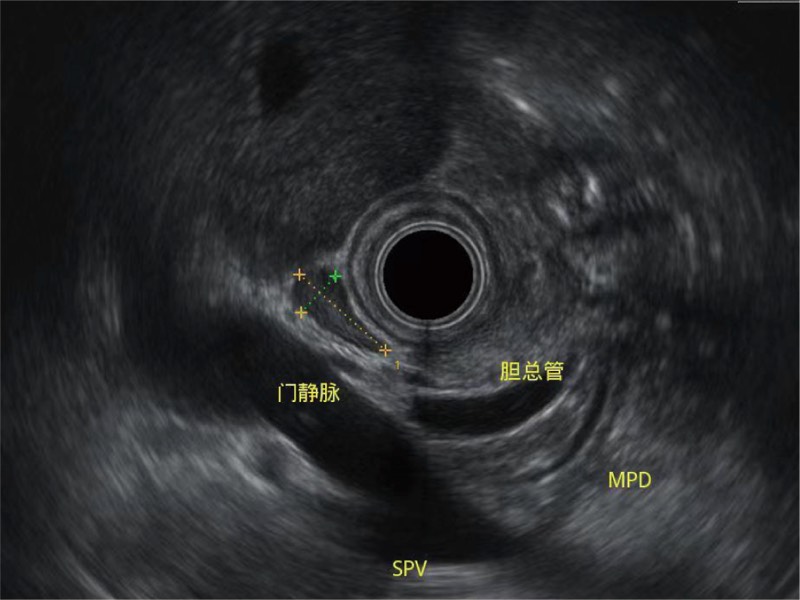

清晰顯示膽總管及周圍血管分布